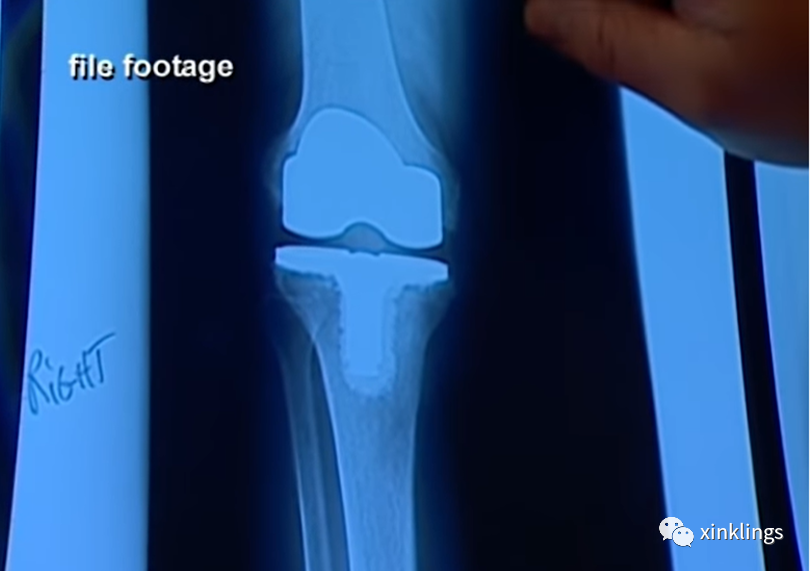

检方向庭上展示了薇琪膝盖的X光片,她右边膝盖的膝盖骨是人工的。据核实,薇琪在死前约18个月时动手术更换膝盖骨,罗恩承认那时他因为薇琪将饼干撒在地上对她动手施暴,致使薇琪膝盖骨粉碎,不得不装上人工膝关节。